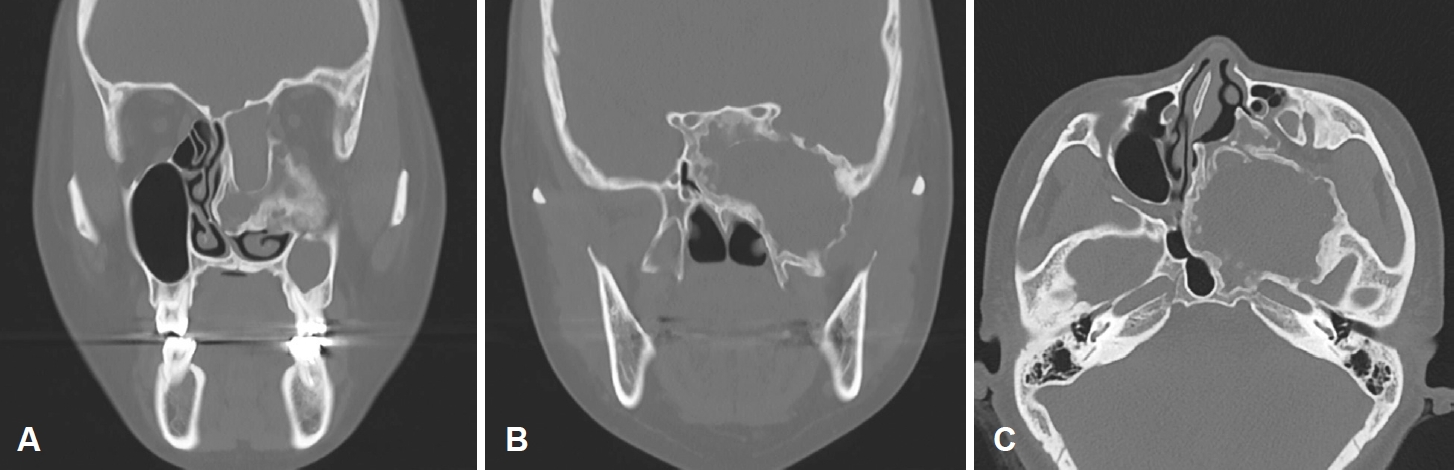

이에 시행한 전산화단층촬영 결과 좌측 사골동을 중심으로 하여 접형동, 익구개와, 익판을 침범한 골성 병변이 관찰되었다. 병변의 경계는 명확하였고 특징적인 간유리음영(ground-glass opacity)을 보여 섬유 이형성증을 의심할 수 있었다. 병변의 크기는 7 cm에 달하였고 그 내부에는 격막이 쳐진 낭성병변이 관찰되었다. 병변의 종괴 효과로 인한 좌측 안와 종이판의 침식과 상악동의 저형성 및 비중격의 우편위가 있었다(Fig. 2).

본 증례는 사골동의 점액낭종을 동반한 섬유 이형성증의 환자로, 그 위치는 사골동을 중심으로 전두동, 접형동의 일부를 침범해 있었다. 안와주위통, 안구돌출 증상을 호소하여 그 치료로 비내시경하 수술을 계획하였다. 섬유 이형성증 내부에는 2개의 구획으로 나뉘어진 점액낭종이 존재하였고 이형성증의 전방 격벽을 제거한 후 점액낭종을 조대하였다. 점액낭종은 부비동구가 차단되는 것이 그 병인이므로, 기존 보고된 바와 같이 섬유 이형성증이 원인일 경우 섬유 이형성증을 감량한 후 이차적인 점액낭종 조대술이 필요하다. 허나 본 증례에서 수술 소견 및 전, 후의 영상학적 소견을 참고하였을 때 점액낭종은 섬유 이형성증의 내부에 온전히 존재하였고 섬유 이형성증의 감량술이 곧 점액낭종의 조대술이 되었다. 이를 통해 섬유 이형성증의 골화 과정에서 비강 점막이 내부로 함입되고 섬유 이형성증 내부에서 점액질이 저류되어 점액낭종이 발생할 수 있다는 새로운 병인을 제시한다. 그 치료로 고전적인 외부 접근법인 아닌 비내시경적 접근만을 통해 점액낭종 조대술을 시행하여 성공적으로 치료하였음을 보고하는 바이다.

NotesAuthor Contribution Conceptualization: Seung Heon Kang, Hyun Jik Kim. Data curation: Seung Heon Kang, Hyunkyung Cha, Seung Cheol Han. Formal analysis: Seung Heon Kang, Hyun Jik Kim. Funding acquisition: Seung Heon Kang. Investigation: Seung Heon Kang. Methodology: Seung Heon Kang. Project administration: Seung Heon Kang. Resources: Seung Heon Kang. Supervision: Hyun Jik Kim. Validation: Seung Heon Kang. Visualization: Seung Heon Kang. Writing—original draft: Seung Heon Kang. Writing—review & editing: Seung Heon Kang. Fig. 1.Endoscopic finding of expansile extruding mass covered with normal mucosa in left middle meatus. Fig. 2.Left ethmoid fibrous dysplasia combined with mucocele (A) eroded lamina papyracea (B) involvement of pterygoid plates (C) hypoplastic left maxillary sinus and right septal deviation. Fig. 3.Endoscopic findings of operation (A) brownish content spilled out from the mucocele (B) visualization of septated mucoceles (asterisks) after removal of anterior wall of fibrous dysplasia (C) after marsupialization. Fig. 4.Histopathologic findings of FD, pathologic report of FD: osteoid trabeculae that are narrow, curvilinear or irregularly-shaped are arranged haphazardly in a background of dense fibroblastic stroma (hematoxylin and eosin, original magnification ×20). FD: fibrous dysplasia. REFERENCES1. Weinstein LS, Shenker A, Gejman PV, Merino MJ, Friedman E, Spiegel AM. Activating mutations of the stimulatory G protein in the McCune-Albright syndrome. N Engl J Med 1991;325(24):1688-95.